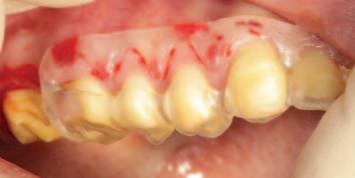

A unilateral sagittal split osteotomy was performed using piezosurgery to protect the nerve. The alveolar nerve, extending from the apical region of the left first and second molars to the mental foramen, was uncovered, and a meticulous dissection was performed to release it from the canal. Notably, rigid paste debris was observed in proximity to and within the nerve canal. The nerve exhibited signs of swelling and was surrounded by granulation tissue (Figures 4 and 5 ).

FIGURE 5: The root canal filling material being removed from the canal.